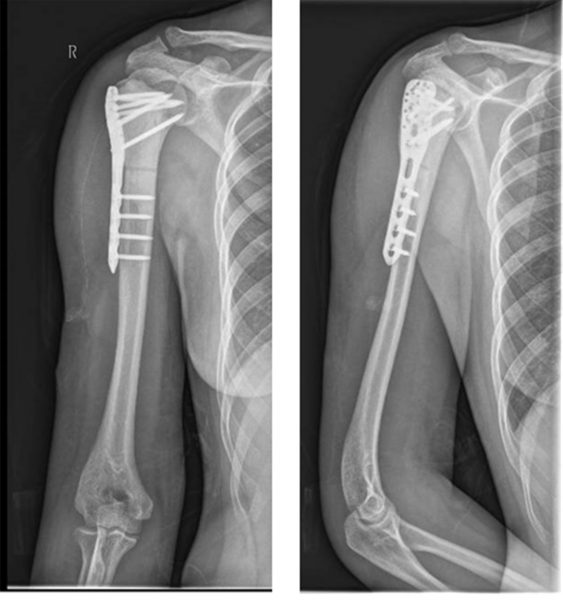

术后X线可见患者右肱骨远端病灶完全清除、骨水泥填充满意、内固定位置可。